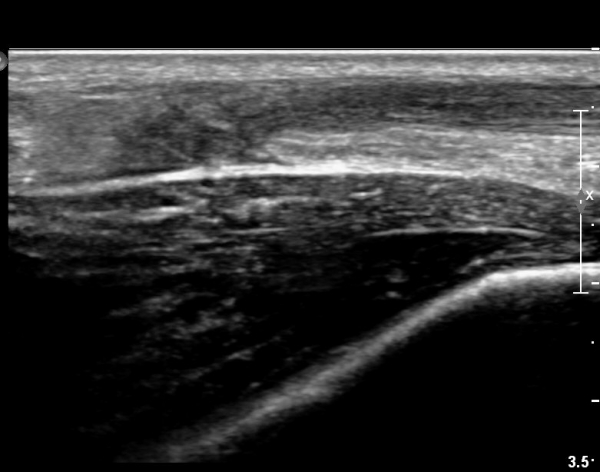

[¹ß¸ñ] simultaneosus tear of GCM and achiles tendon

pain on rt. leg( du: 1 day)

abrupt leg pain developed during foot volleyball

he walk with severe limping with no weight bearing on rt. leg. on examination, there is local tendernes at GCM and achiles tendon, severe pain with ankle dorsiflexion.

ÃÊÀ½ÆÄ °Ë»ç